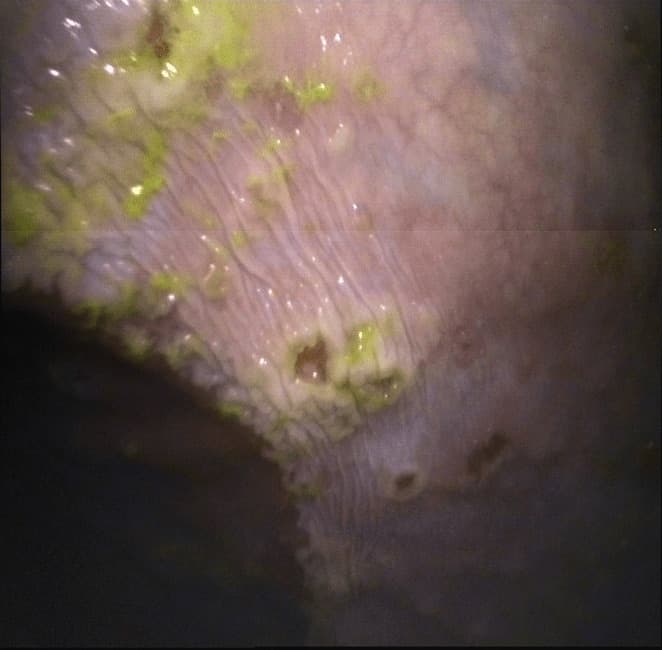

To protect the stomach lining from the natural acid environment, there are specialised cells, foveolar cells, which produce a protective mucin coating. The mucin secretion stops if the stomach contains too much acid. The stomach lining will then become exposed to a rising acidity as a result of which specific bacteria can thrive eating the stomach lining which will eventually lead to ulcers.